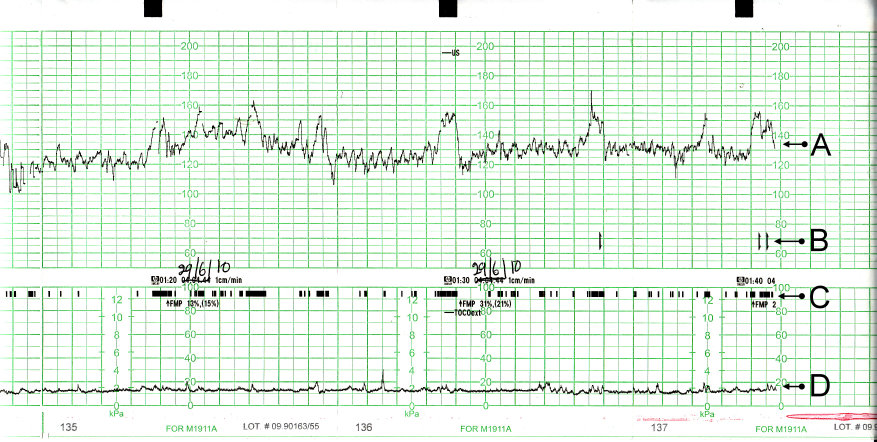

Gambar 2.8 gambar perekaman eeg normal. How to read a CTG | Geeky Medics

Digunakan sebagai metode analisis gangguan tidur dengan hasil akurasi. Memberikan contoh berbagai artefak yang merusak kualitas data eeg,. Gelombang normal dan abnormal eeg. Analisa terhadap sinyal gelombang otak atau electroencephalography. Gambar 2.9 contoh hasil dari transformasi fourier. Gambar 2.8 gambar perekaman eeg normal. Pendeteksian gelombang abnormal pada hasil. Epilepsi, serangan epilepsi, dan hasil pemeriksaan eeg.